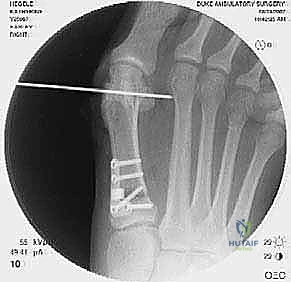

2. التصوير الشعاعي المتقدم

- الأشعة السينية مع تحمل الوزن (Weight-bearing X-rays): صور من الأمام، الجانب، والزوايا المائلة لتقييم زوايا العظام تحت تأثير وزن الجسم.

- تصوير السمسمانيات (Sesamoid view): لمعرفة ما إذا كانت العظام السمسمانية قد خُلعت من مكانها.

- الأشعة المقطعية (CT Scan): في الحالات المعقدة، يستخدم الدكتور هطيف الأشعة المقطعية ثلاثية الأبعاد لتقييم التئام العظام السابق، ومواقع المسامير القديمة، ودرجة خشونة المفاصل بدقة متناهية.

جراحة المراجعة هي عمل فني وهندسي معقد. إليك كيف يقوم الأستاذ الدكتور محمد هطيف بإجرائها خطوة بخطوة، معتمدًا على أحدث التقنيات العالمية:

الخطوة 1: التعامل مع الشق الجراحي القديم وإزالة المعادن

- يبدأ الدكتور هطيف بفتح الجلد، غالبًا باستخدام الشق الجراحي القديم لتقليل الندبات، مع استئصال الأنسجة المتندبة (Scar excision) بحذر شديد لحماية الأعصاب والأوعية الدموية.

- يتم تحديد مواقع المسامير أو الشرائح المعدنية من الجراحة السابقة وإزالتها (Hardware Removal). قد تكون هذه الخطوة صعبة إذا نما العظم فوق المسامير.

إذا كان الفشل ناتجًا عن تصحيح غير كافٍ في الجراحة الأولى، وكان المفصل لا يزال سليمًا (لا توجد خشونة شديدة)، يقوم الدكتور هطيف بإجراء قطع عظمي جديد (مثل تقنية Scarf أو Chevron) لإعادة توجيه العظم وتثبيته بمسامير تيتانيوم حديثة لا تسبب تهيجًا.

ب. عملية لابيدوس (Lapidus Procedure - TMTJ Arthrodesis)

إذا كان سبب التكرار هو "فرط الحركة" في مفصل منتصف القدم (TMTJ)، فإن الحل الوحيد لمنع التكرار المستقبلي هو دمج (إيثاق) هذا المفصل. يزيل الدكتور هطيف الغضروف من المفصل، يصحح زاوية العظم، ويثبته بشريحة معدنية قوية ومسامير حتى يلتحم العظمان معًا. هذه العملية تعالج أصل المشكلة من الجذور.

في هذه العملية، يتم إزالة الغضروف التالف من مفصل الإصبع الكبير، ودمج العظام معًا في وضع مستقيم قليلاً للأعلى للسماح بالمشي الطبيعي. يتم التثبيت باستخدام شريحة ومسامير متقاطعة. النتيجة هي إصبع مستقيم، خالٍ تمامًا من الألم، ولا يمكن أن يعود للتشوه أبدًا.